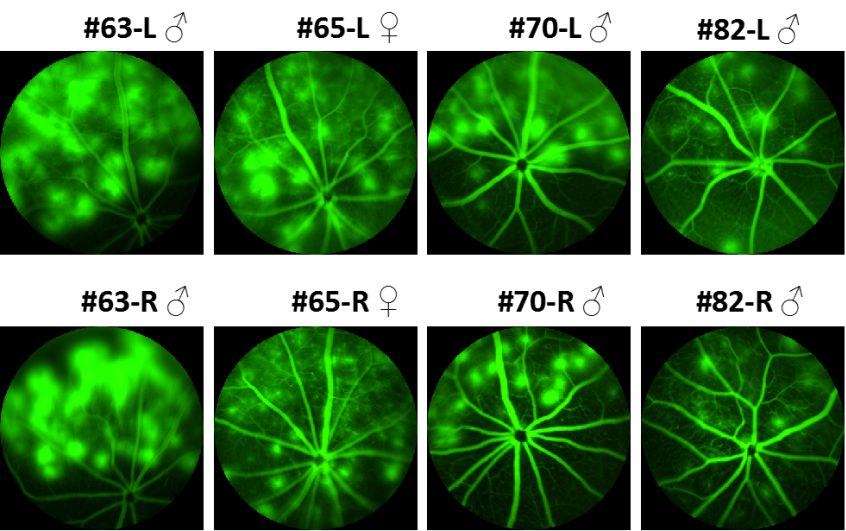

FFA(眼底荧光血管造影)结果显示:F2小鼠能复现F0和F1表型。

hVEGF小鼠(F2)眼底荧光血管造影结果